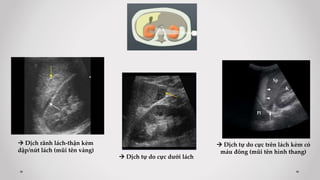

 Mặt cắt 3: liên sườn Trái

Trả lời các câu hỏi:

- Có dịch rãnh lách – thận?

- Chấn thương lách? Thận (T)?

 Dịch rãnh lách-thận kèm

dập/nứt lách (mũi tên vàng)

 Dịch tự do cực dưới lách

 Dịch tự do cực trên lách kèm có

máu đông (mũi tên hình thang)

 Mặt cắt 2: liên sườn Phải

- Có dịch rãnh gan-thận (Morrison)?

- Chấn thương gan (P)? Thận (P)?

 Dịch rãnh Morrison

 Dịch rãnh Morrison + Dịch trên gan